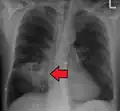

Études d'imagerie

Les abcès pulmonaires sont souvent d'un seul côté et concernent les segments postérieurs des lobes supérieurs et les segments apicaux des lobes inférieurs, car ces zones dépendent de la gravité en position couchée. La présence de niveaux air-fluide implique une rupture dans l'arbre bronchique ou, rarement, la croissance d'un organisme gazogène.[réf. nécessaire]

Abcès pulmonaire sur CXR